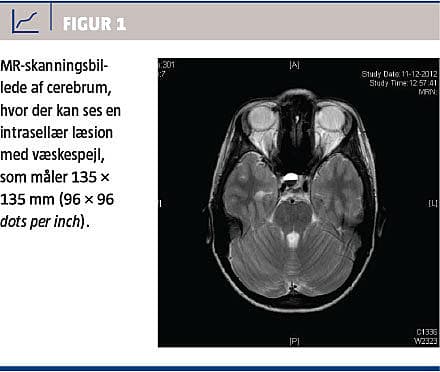

En 17-årig ung kvinde blev henvist med sekundær menostasi, hovedpine samt intermitterende sløret syn igennem fem måneder. S-prolaktinniveau var ved egen læge målt til 1.800 IE/l (referenceværdi: 35-600 IE/l). Patienten var, fraset svær hovedpine, alment upåvirket og ved objektiv og neurologisk undersøgelse fandt man normale forhold. Paraklinisk fandt man normale væske-, infektions-, lever-, og thyroideatal. Niveauerne af østradiol (0,14 nmol/l), follikelstimulerende hormon (9,4 IE/l) og luteiniserende hormon (7,8 IE/l) var inden for normalområder for såvel follikulær fase, luteal fase som midtcyklys. Øjenundersøgelse og synacthentest viste normale forhold. En MR-skanning af cerebrum viste et 12 × 9 × 12 mm stort hypofyseadenom med høje intensiteter på både T1- og T2-vægtede sekvenser. Desuden sås der væskespejl, som tolkedes som blødning (Figur 1). Patienten blev behandlet med tbl. cabergolin 0,5 mg én gang ugentligt. Ved kontrol efter seks uger var prolaktinniveauet normaliseret. Patienten havde regelmæssige menstruationer, og hovedpinen var reduceret betydeligt.